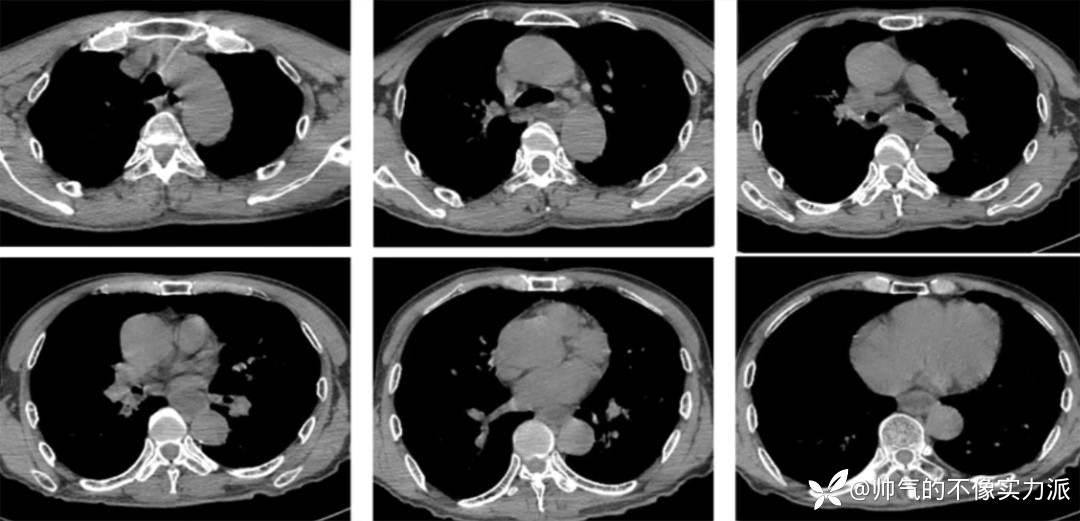

- 与入院前胸部CT相比,患者上肺结节斑片及磨玻璃样渗出影,双侧下肺重力依赖区明显实变影,出现支气管充气征(图2)。

图2 患者胸部CT(2020-12-09)

- 考虑患者有无肺栓塞可能?故进一步完善CT肺动脉造影(CTPA)检查,结果提示右肺下叶动脉内低密度充盈缺损,考虑栓子形成可能。双肺炎症并部分肺实变,建议治疗后复查。

- 2020年12月12日,复查胸部CT:双上肺磨玻璃影明显增多,下肺重力依赖区依然存在实变影,少量胸腔积液(图3)。

图3 患者胸部CT(2020-12-12)